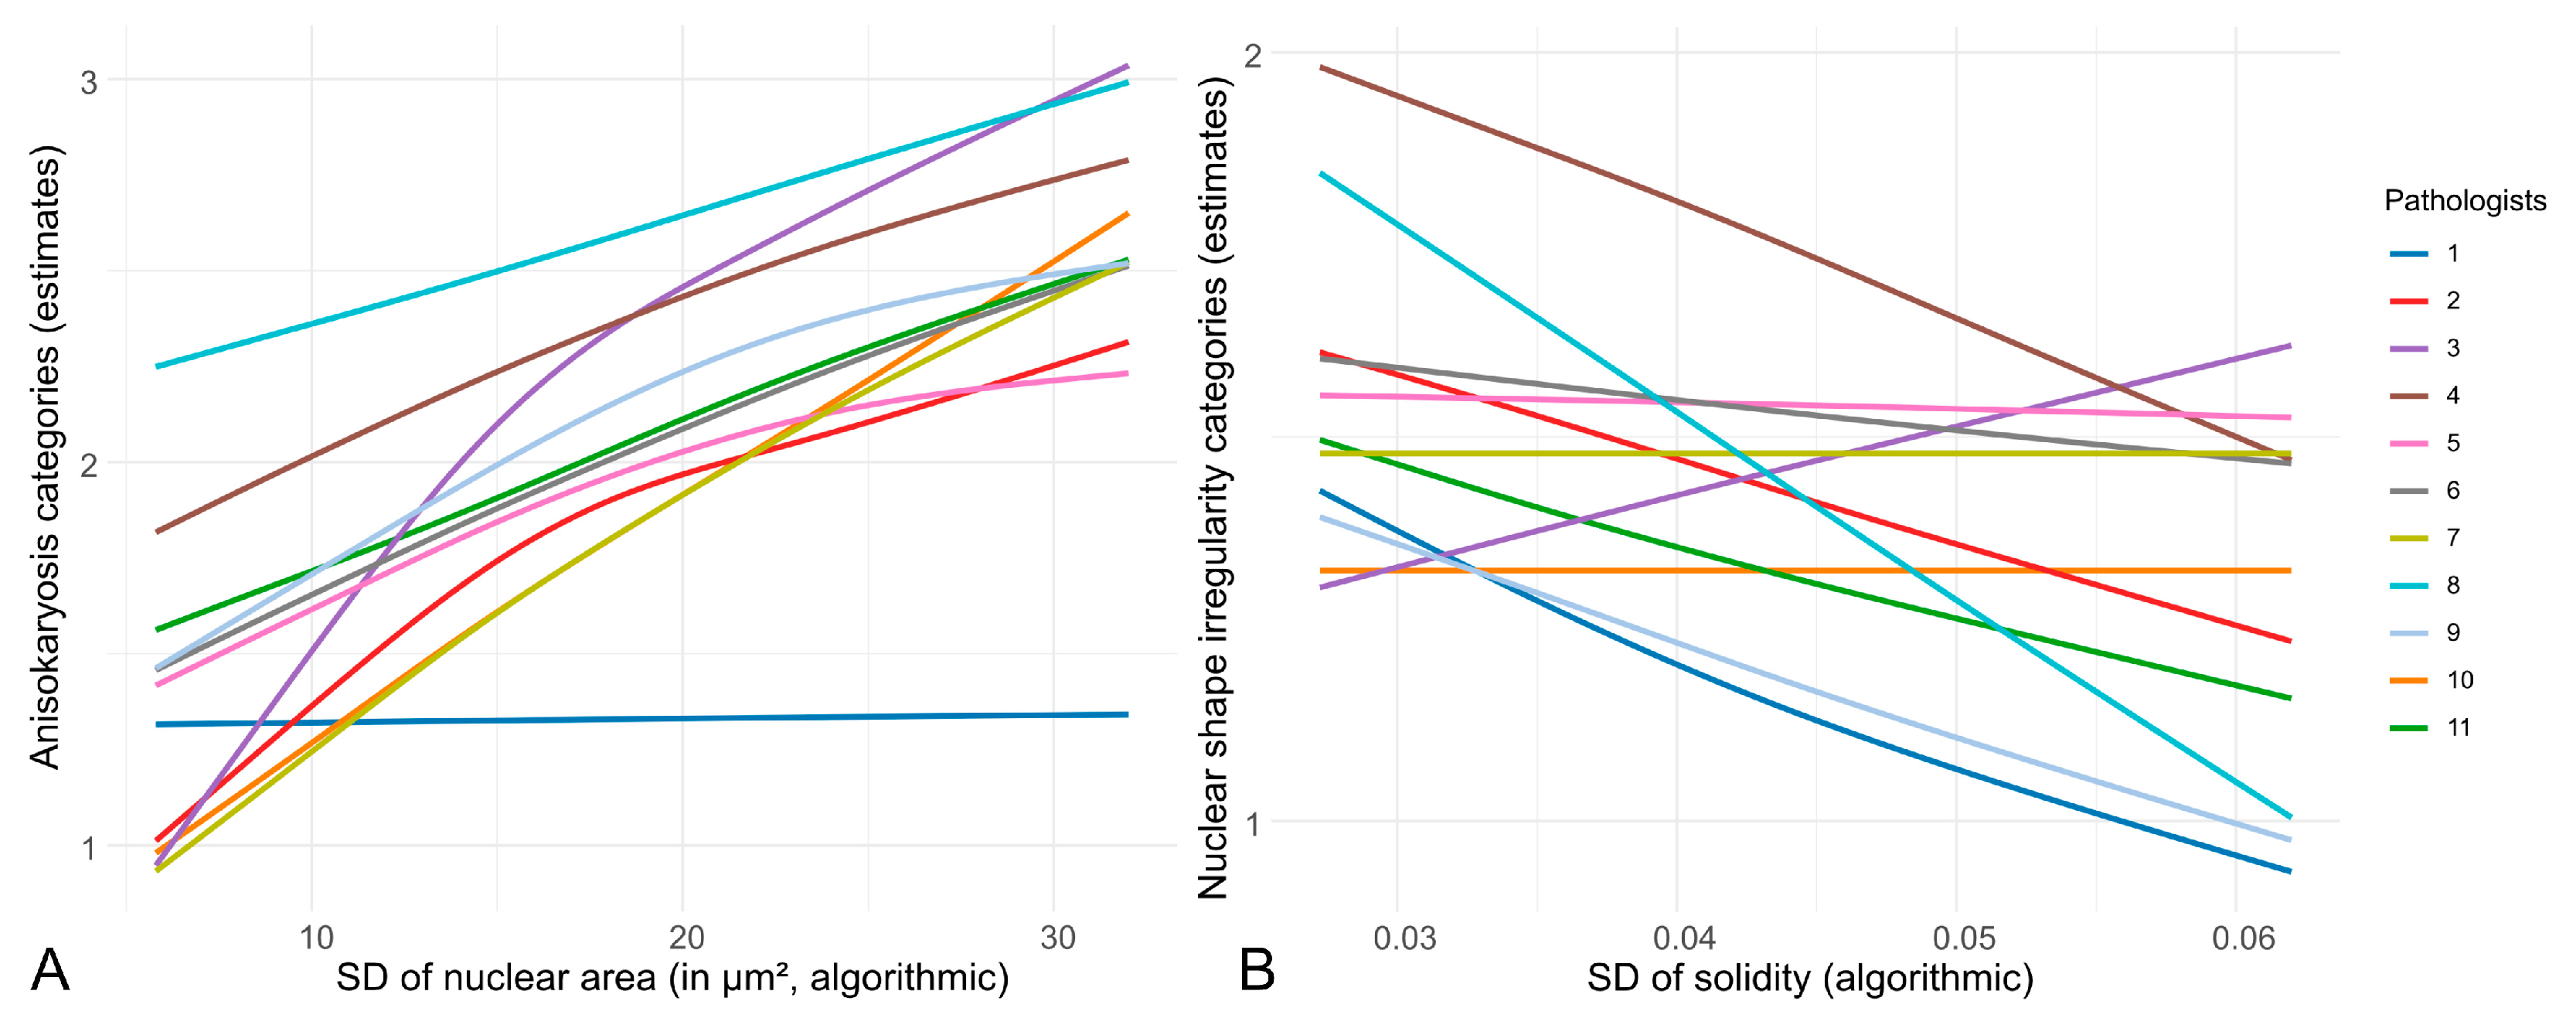

- Inter-observer reproducibility of nuclear pleomorphism estimates between pathologists is low in cPC, justifying the investigation of nuclear morphometry.

- Algorithmic morphometry is able to accurately measure nuclear size and shape parameters.

3.1. Inter-Observer Reproducibility of Nuclear Pleomorphism Estimates

3.2. Test Accuracy of Algorithmic Morphometry

- We have demonstrated the low inter-observer reproducibility of nuclear pleomorphism estimates among pathologists in cPC. Nuclear morphometry presents a reasonable approach to overcome this limitation.

- The algorithm’s segmentation ability was good for nuclear size parameters and acceptable for shape parameters. Future studies may benefit from implementing filters and/or optimizing the algorithm to improve the model’s accuracy.

4.1. Inter-Observer Reproducibility

4.2. Test Accuracy of Algorithmic Morphometry